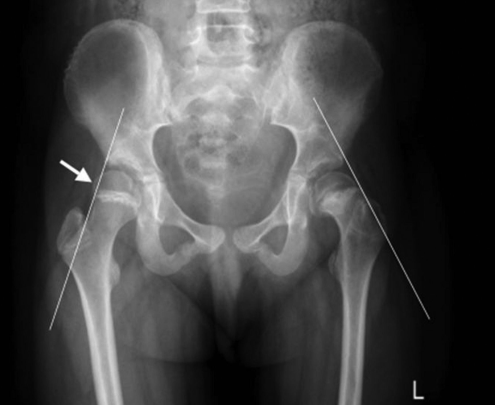

This image shows

Perthe’s disease

CDH

SUFE

Pes planus

Talipes equinovarus

A